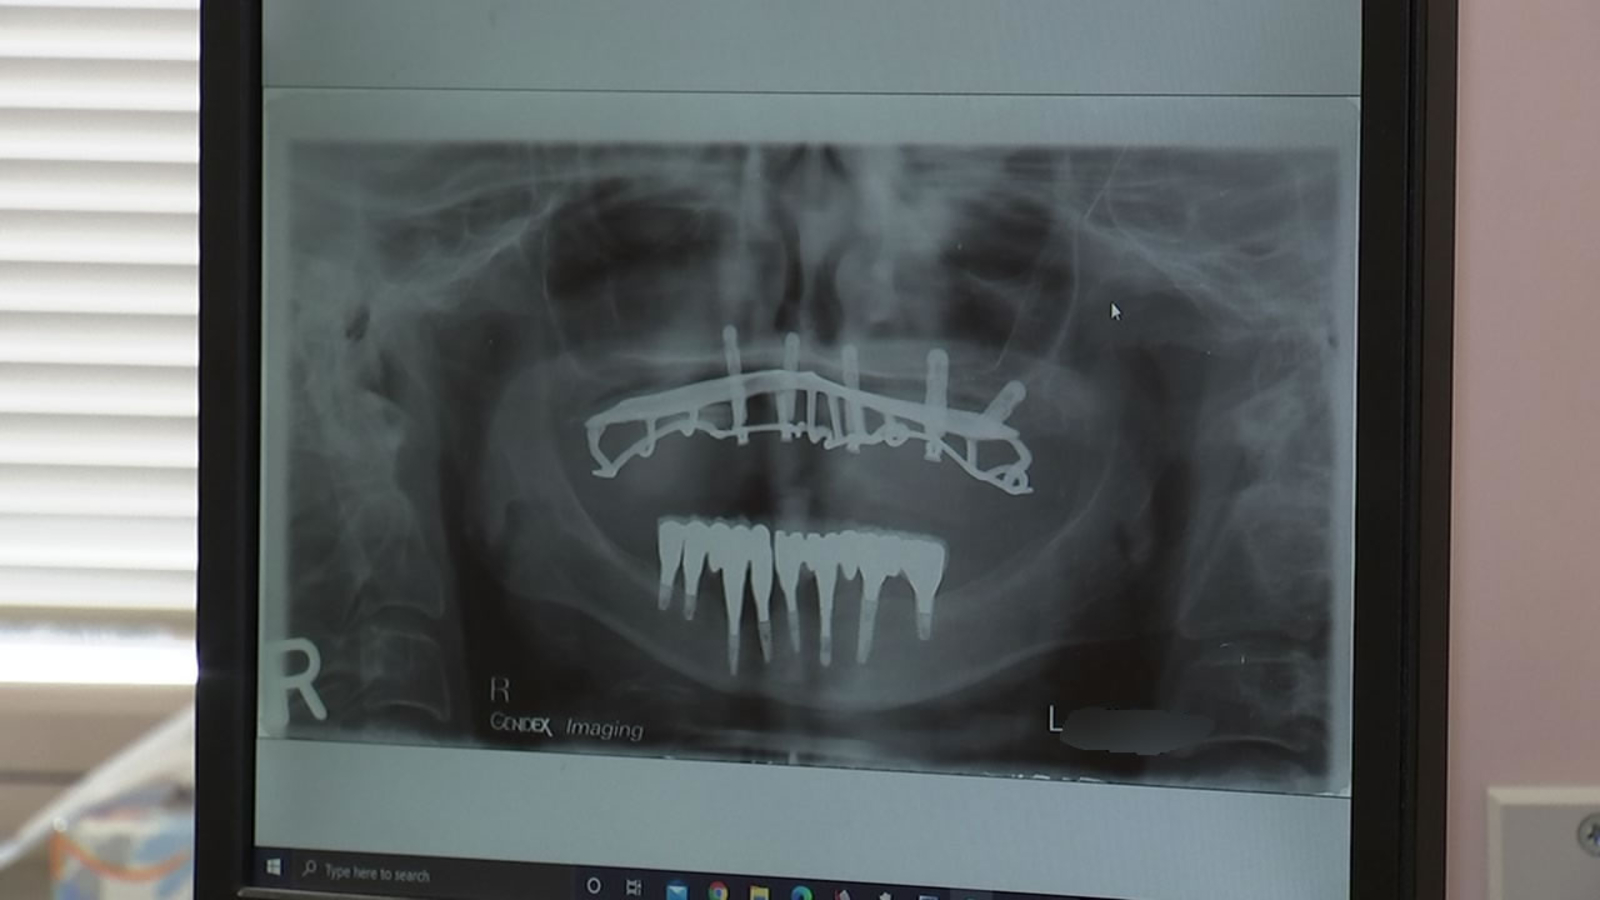

"Our patients that we're seeing have very unusual fractures," said Dr. Mueller, pointing to a photo of an otherwise completely healthy tooth, split in half. "It's tremendous force to cause that kind of fracture of your own teeth."

Dr. Wagnild said before the coronavirus pandemic, he would see teeth with big fillings and decay chip off. But now, he's seeing solid, healthy teeth fracturing.

"We used to see one every couple years maybe. Now we're seeing them routinely," said Dr. Wagnild.

Dr. Nidhi Pai, a cosmetic and family dentist, said pre-pandemic, she would see one to two tooth fractures a week. Now she's seeing one to two a day, and in June and July she said was seeing four to five a day.